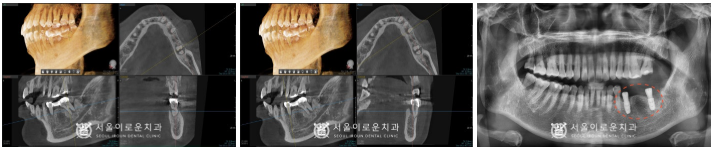

그리고 제일 불편감을 호소하셨던

왼쪽 아래 브릿지 보철물(#35,37)로

수복된 치아를 발치하고나서

주변 염증조직을 깨끗하게 제거한 뒤

뼈이식을 동반하여

임플란트 즉시 식립을 진행하였습니다.

발치 후 즉시 식립을 하게 되면

잇몸 조직의 손상과 출혈, 붓기도 적어

통증도 감소되며

치료 기간이 단축되는 장점이 있는데요.

임플란트 즉시 식립은

누구에게나 다 적용되는 것은 아니며,

구강 내 상황을 정밀하게 체크한 뒤

의료진의 판단하에

즉시 식립 여부를 결정하게 됩니다.

발치 후 즉시 임플란트를 진행하는 날

왼쪽 위아래 사랑니(#28,38)도

같이 발치를 진행하였으며,

왼쪽 잇몸이 어느 정도 아문 뒤

오른쪽 사랑니(#18,48)도

발치를 도와드렸고,

임플란트와 주변 치조골이

단단하게 결합되기를 기다리는 동안

다른 치료를 도와드렸는데요.

임플란트 식립 2달 반 후

osstell beacom이라는

골 유착을 확인할 수 있는 장비를 활용해

골 유착 정도가 안정 값임을 확인하고

보철 과정을 진행하였습니다.

임플란트와 크라운을 연결할 때

기둥 역할을 하는 지대주인 abutment를

환.자분 구강 내 상황에 맞는

맞춤형 지대주인

custom abutment를 체결한 뒤

자연치아의 강도와 제일 유사하고

심미적인 지르코니아 크라운으로

임플란트 보철 과정을 마무리하였습니다.